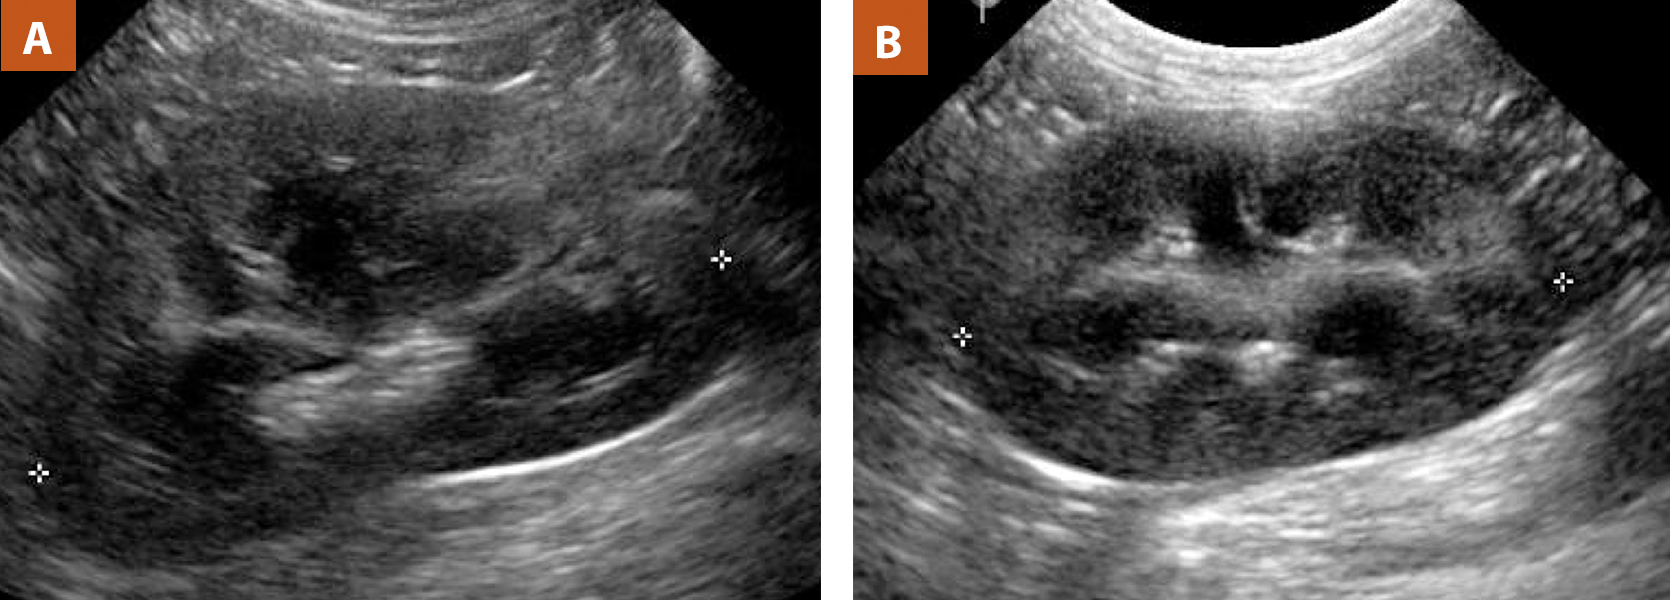

Интраренальная лоханка: рентгеновские снимки и примеры

Раздел: Фотоэссе